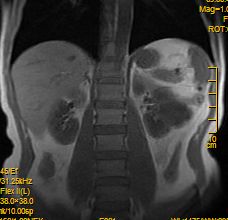

冠状位是压脂序列?

请发动态强化扫描及延时强化扫描!

标题: MRI2883:左肾占位性病灶,请大家来会诊!

左肾占位性病灶,请大家来会诊!

考虑左肾囊性肾癌,多囊性肾瘤待排。

考虑左肾囊性肾癌,多囊性肾瘤待排。建议增强。

左肾癌囊变。